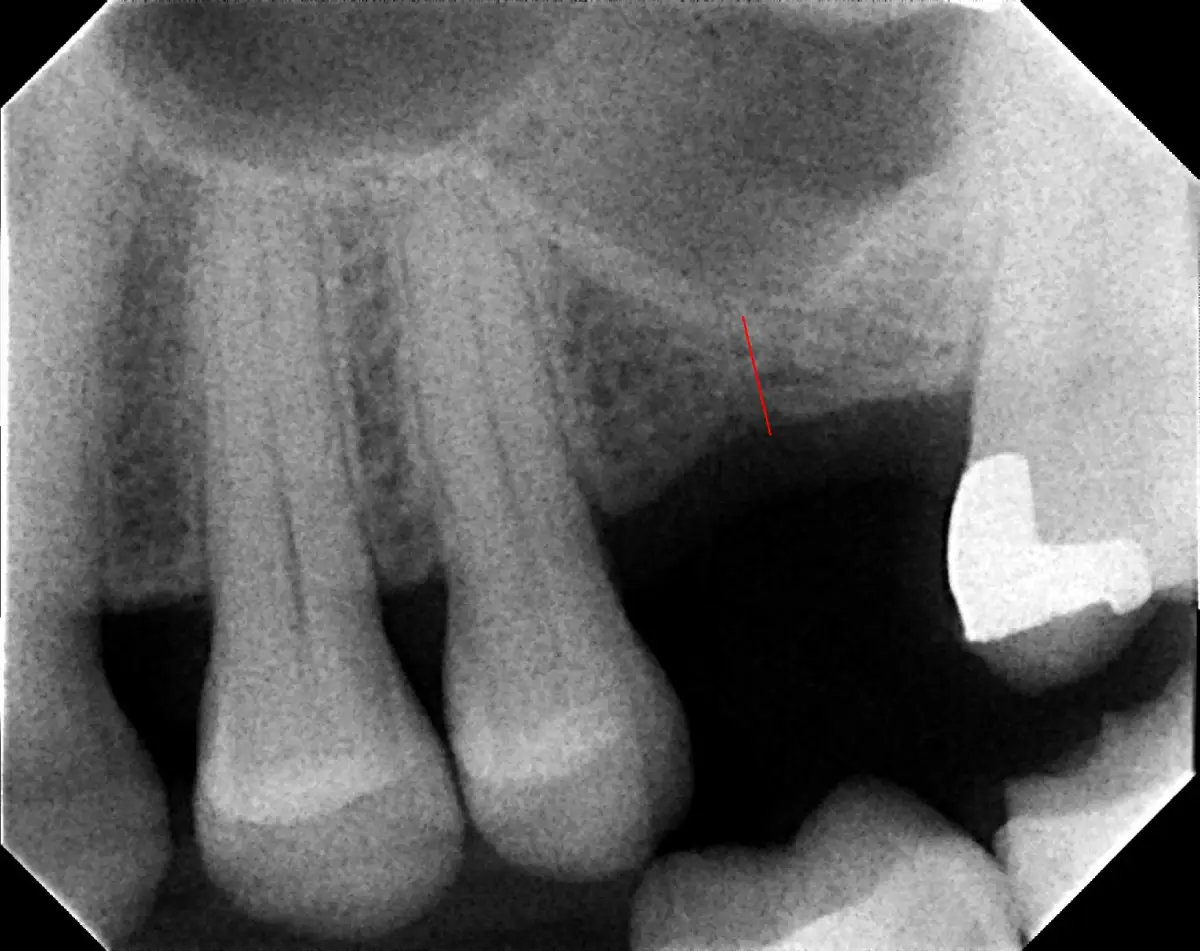

Bone Graft

before

after